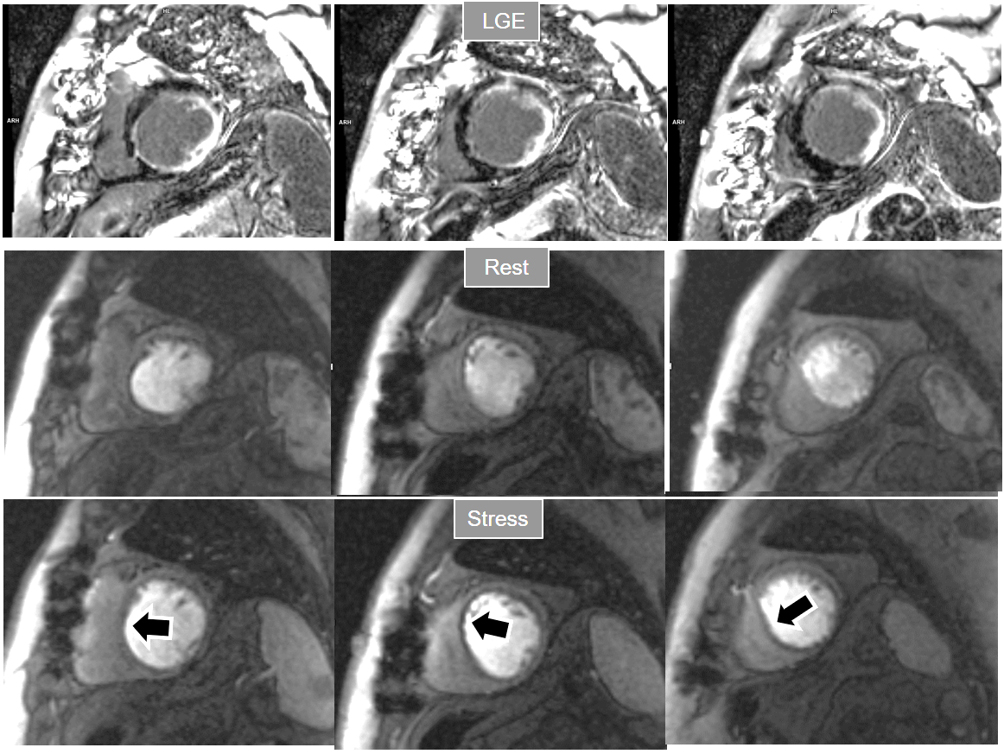

When considering both, the variability of rest perfusion in the presence of previous MI, and the rather low sensitivity of partially reversible defects, the interest in knowing the actual extension of fixed defects emerges. An option to address the issue is to invert the order of perfusion studies in patients with previous MI, performing the rest study first. This allows for a reliable delineation of the fixed defect that can be easily subtracted from the inducible one, when present (Fig. 18). Moreover, in the case of patients with advanced, severe CAD, in whom a combination of infarcted regions and underperfused territories can be expected, a basal rest perfusion study followed by the stress one is even more helpful (Fig. 19). Certainly, the presence of CA in an area of MI after the first rest perfusion study may contaminate the SI of the second one, but this does not preclude the detection, or exclusion, of newly induced defects (Fig. 20).

Fig. 18.Rest/Stress perfusion in chronic myocardial infarction. Patient with previous myocardial necrosis involving most of the LV segments, mainly subendocardial in the anterior and septal regions, and transmural in the lateral wall, as shown in the LGE images (upper panel). The rest perfusion study, performed in first place (middle panel), shows a diffuse subendocardial defect, while, at a subsequent stress study (lower panel), a fair increase in transmurality and extension of the antero-septal defect is seen (arrows) indicating peri-infarction ischemia, while the lateral one remains unchanged. Note the lack of interference of the previous dose of CA on the tissue contrast of the stress study.

Fig. 19.Rest/Stress perfusion in chronic myocardial infarction. Upper panel: LGE study showing subendocardial necrosis of the infero-lateral segments (white arrows). Middle panel: rest perfusion study performed in first place showing a defect extending far beyond the limits of the actual MI (black arrows), indicating impaired perfusion at rest of non-infarcted territories (i.e., myocardial hibernation). Lower panel: subsequent stress study showing an increase in extension and transmurality of the inferior defect (large black arrows) and, also, the appearance of and additional induced defect at the anterior wall (small black arrows). Again, the stress study is not interfered by the previous CA administration.